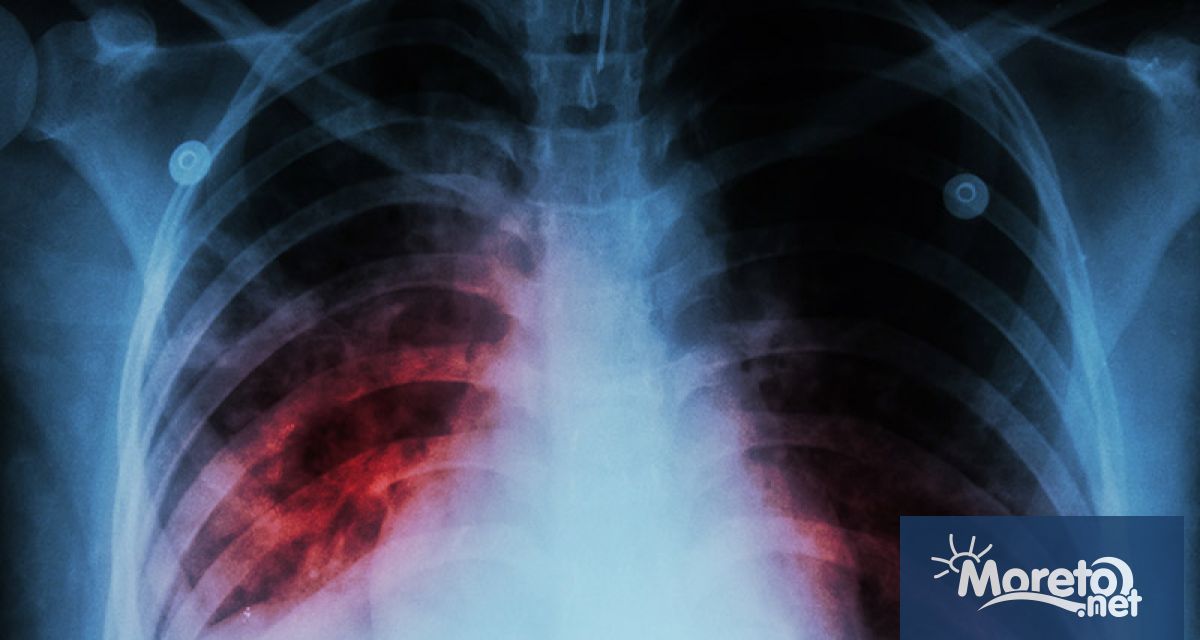

Над 4 хил. годишно се разболяват от рак на белия дроб у нас - над 3 хил. от тях са мъже

Всяка година в страната ни се диагностицират 4250 нови случая на рак на белия дроб, като 3260 са сред мъже. Това каза пред журналисти проф. Асен Дудов, председател на Българското онкологично дружество, цитиран от БТА. По думите му тази локализация е водеща причина за смърт от онкологично заболяване в България. Причини за повишаване на случаите на рак на белия дроб са тютюнопушене, излагане на азбест, пасивно пушене, генетични предпоставки и други.

Повечето случаи на болестта се диагностицират късно - в трети или четвърти стадий, което възпрепятства възможностите за лечение. Късната диагноза е причината за високата смъртност, като 80 на сто от пациентите загиват в рамките на 1 година след диагностицирането.

Целите, които биха могли да ускорят диагностиката и лечението, са повишаване на информираността на населението, намаляване на времето между консултациите и началото на лечението, както и усъвършенстване на програмите за скрининг сред рисковите групи.